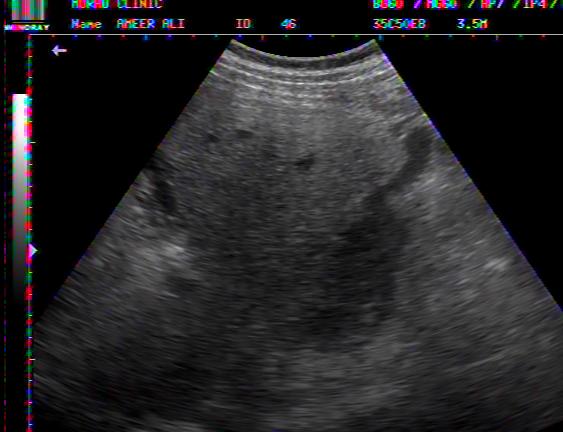

FLUID AROUND LIVER IN DHF

PLASMA FLUID AROUND LIVER IN DHF